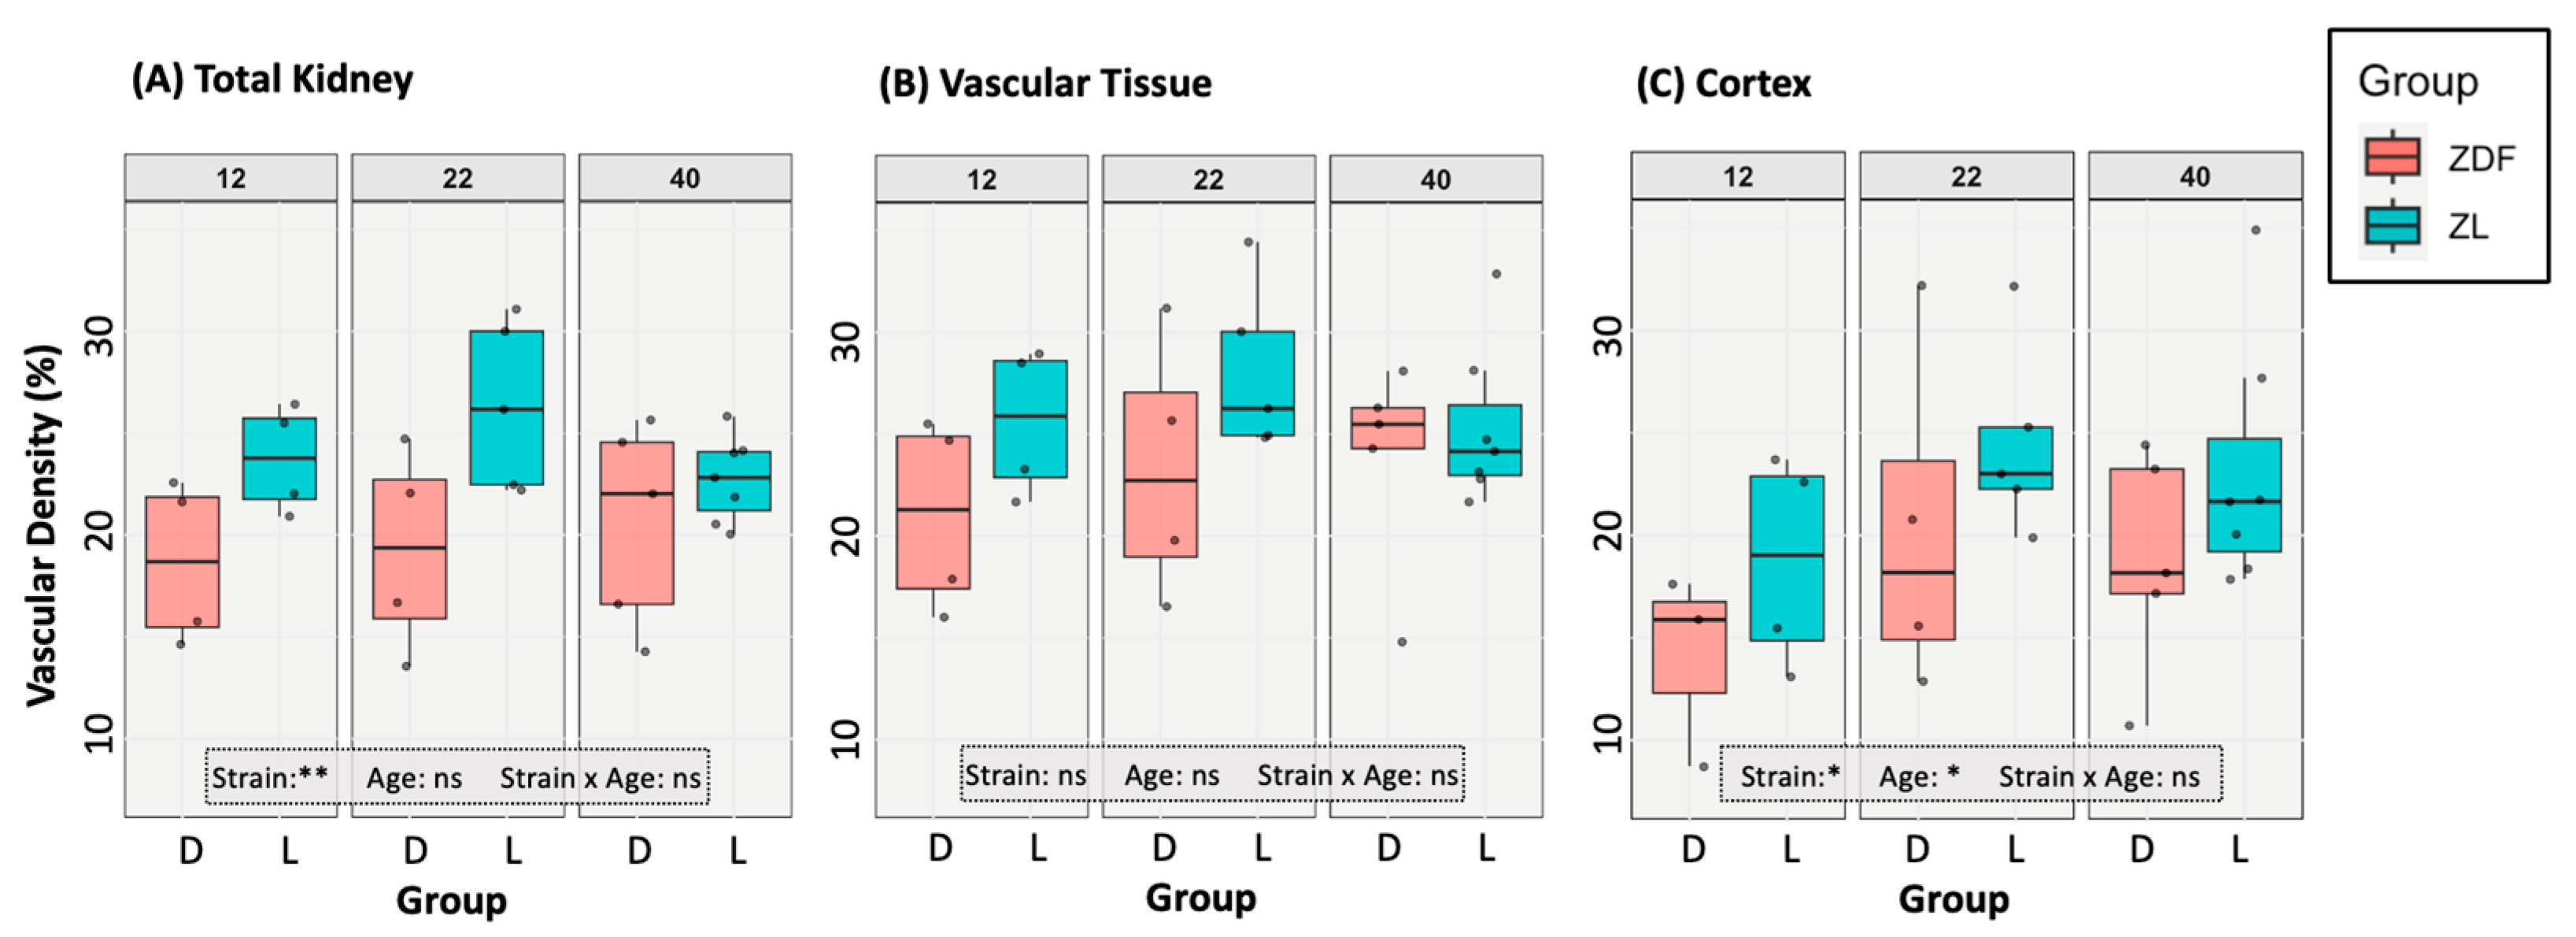

3.2. Vascular Modelling of Diabetic Kidney Disease

3.4.1. Renal Vascularity